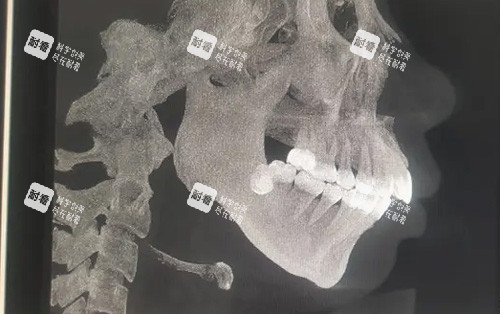

這些逆襲病例背后,是周會(huì)喜團(tuán)隊(duì)20年磨一劍的“硬核技術(shù)”。作為南方醫(yī)學(xué)大學(xué)口腔頜面外科主管醫(yī)師、廣東省整形美容團(tuán)隊(duì)理事,他手里的“家伙事兒”可不止手術(shù)刀——CT影像+3D打印導(dǎo)板,能把頜骨截骨誤差控制在0.1毫米內(nèi),“就像給骨頭裝了個(gè)GPS,避開(kāi)神經(jīng)血管,連‘歪嘴’都能精細(xì)復(fù)位!”

除了手術(shù)費(fèi),還有術(shù)前檢查(X光片、3D建模,約2000-5000元起)、麻醉費(fèi)(全麻約5000-1萬(wàn)元起)、材料費(fèi)(鈦板固定,約1萬(wàn)-2萬(wàn)元起)、術(shù)后改善(牙齒矯正、復(fù)查,約2萬(wàn)-5萬(wàn)元起)。網(wǎng)友“小橘子”算過(guò)一筆賬:“我做的中階方案,手術(shù)費(fèi)7萬(wàn),加上檢查、麻醉、材料,總共花了9萬(wàn)8,但結(jié)果值這個(gè)價(jià)——現(xiàn)在臉對(duì)稱了,咬合正常了,連說(shuō)話都更有底氣了!”